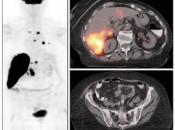

The “Sponge Effect”

Describes the common phenomenon whereby circulating FDG available for tumoral uptake is decreased due to excessive FDG uptake in non-target tissues.

This “Sponge Effect” (soaking up of available FDG by non-target tissues) leads to false negative assessment of tumors — decreasing both visual appreciation and SUV assessment of lesions.

The most common etiologies for this phenomenon include:

- Poor Patient Preparation (non-fasting state, vigorous exercise, insulin administration) [Fig. 1]

- FDG Extravasation [Fig. 2]

- Extensive Brown Fat Activity

- Metformin-Induced Bowel Uptake [Fig. 3]

- Marked Reactive Marrow Uptake

- Extensive Tumor Uptake [Fig. 4] [Fig. 5]

In each of these situations, excessive non-target uptake of FDG decreases available FDG uptake by tumors in the body.